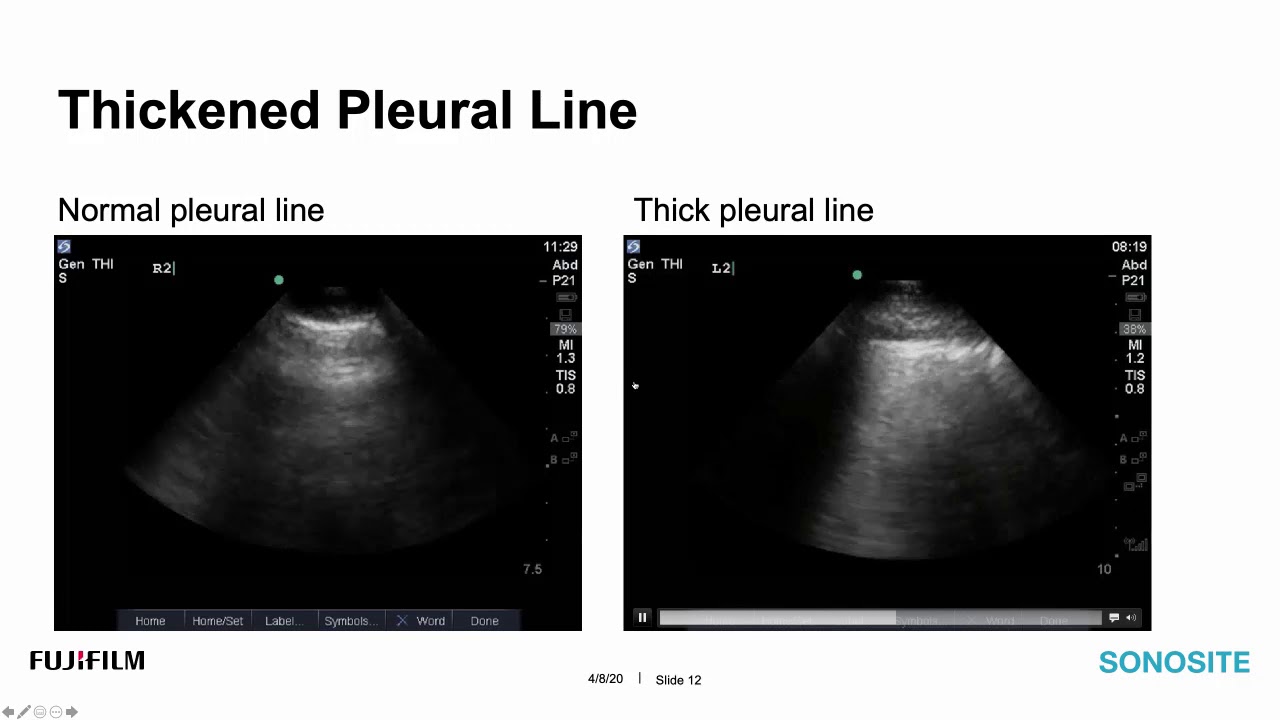

Covid 19 and Lung Ultrasound

These are the latest Covid 19 and Lung Ultrasound images from around the world.